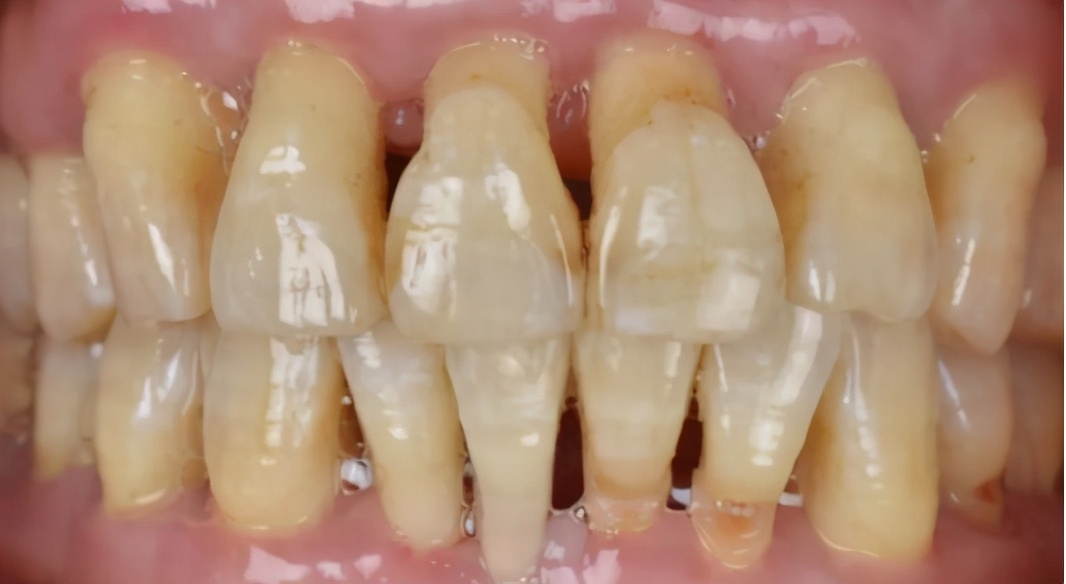

那成年人呢?成年人当然也可以做矫正,二三十岁,风险一般不大,但要评估自己的工作和正畸时间是否有冲突,在牙齿上粘金属托槽是否影响形象和对工作有没有影响。牙周风险一定要评估,尤其是中年或者老年正畸患者。

(牙周病患者的口内情况,牙龈牙槽骨萎缩,前牙松动外展)